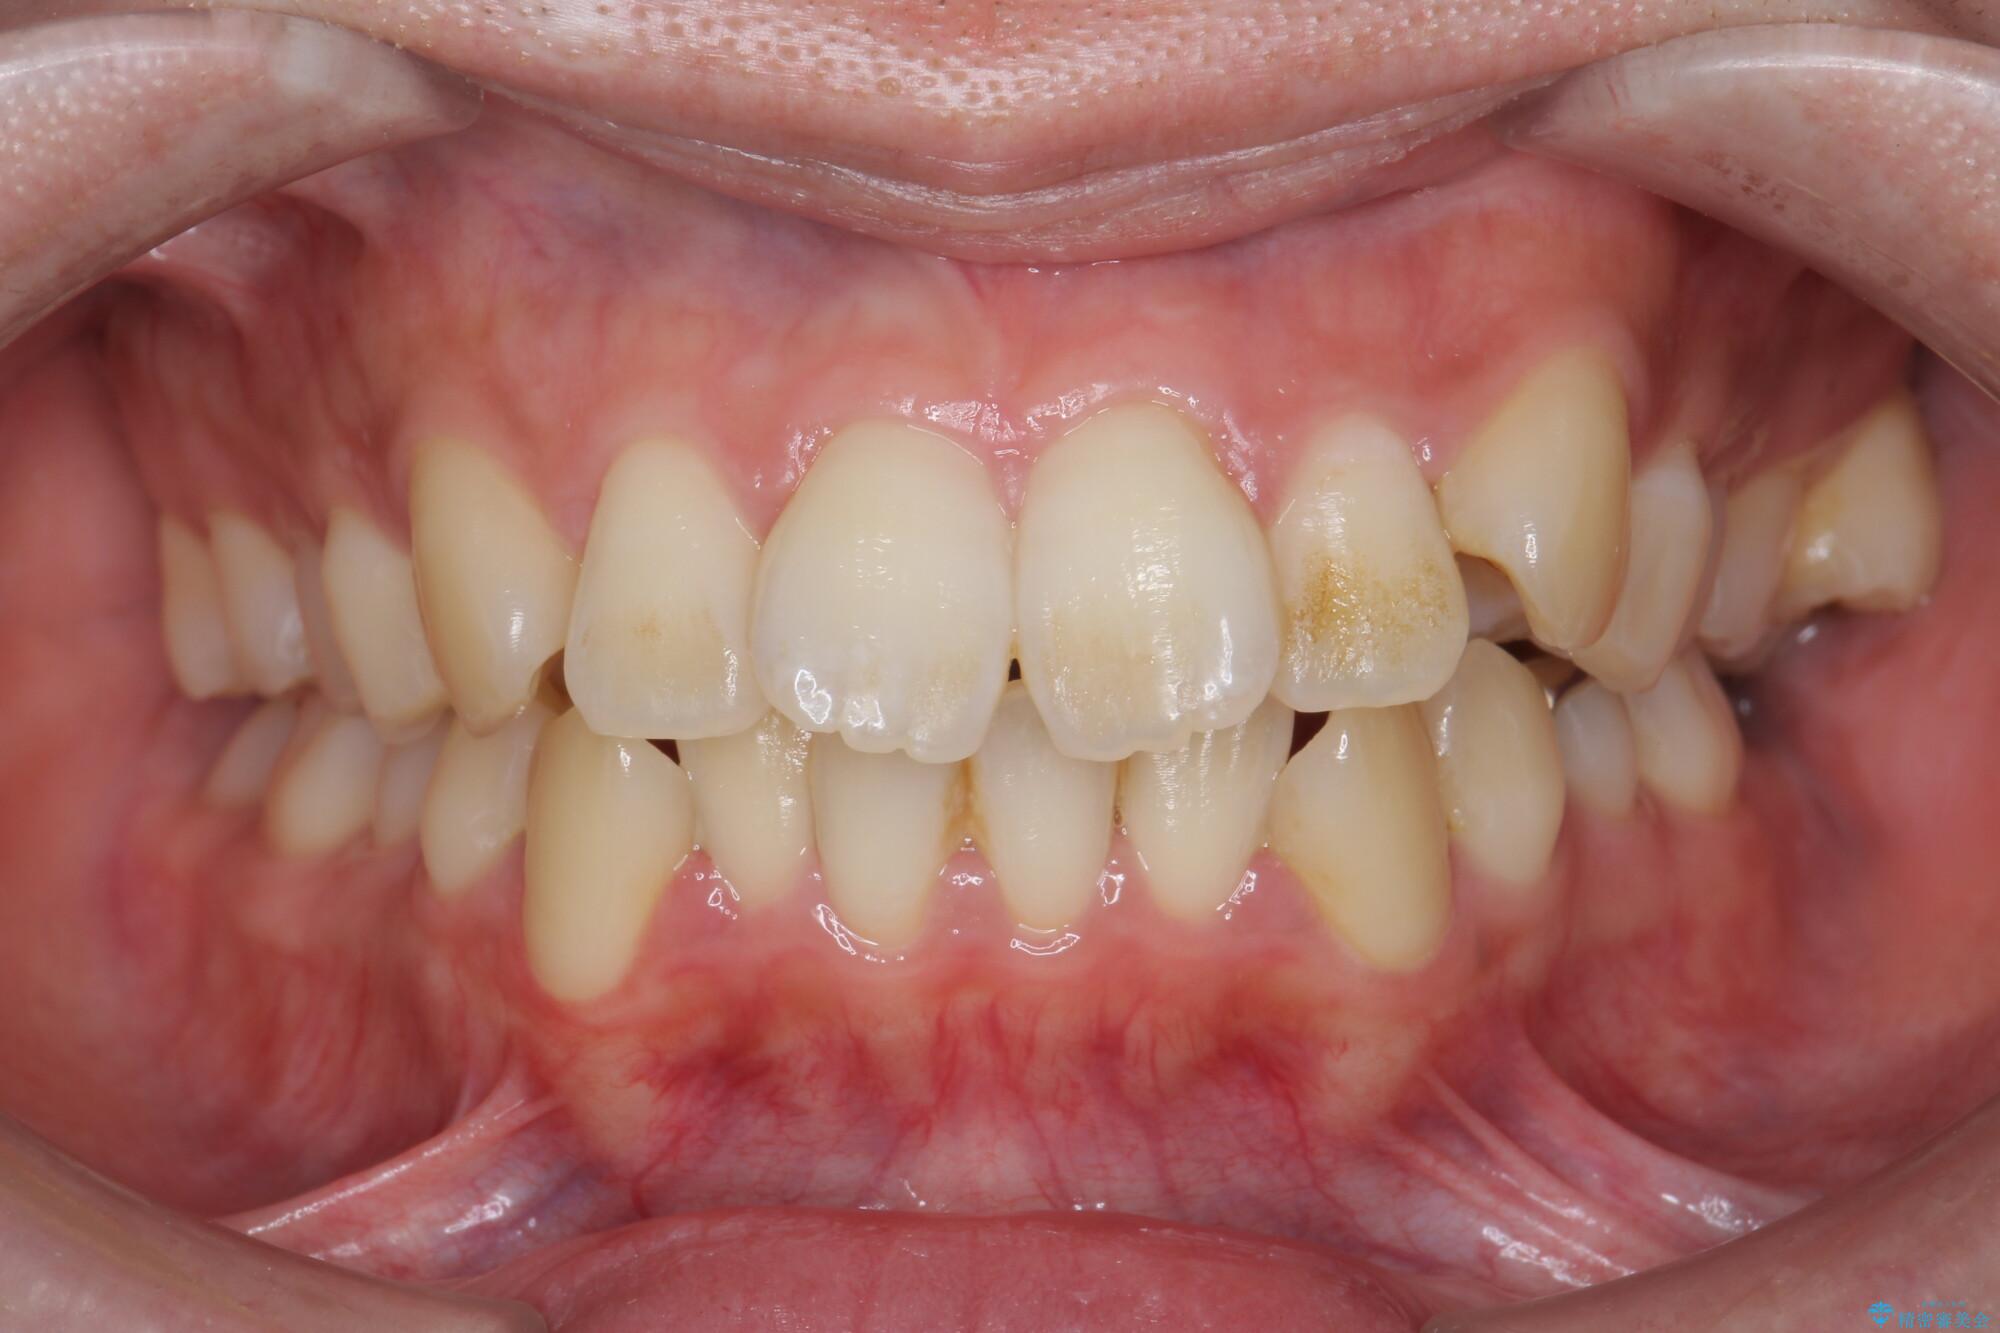

前歯のガタつきの改善を主訴にご来院されました。 特に犬歯の傾きが気になるとのことでした。

犬歯がかなり手前に傾いていましたが、ガタつきはそれほど強くないため非抜歯でマウスピース矯正が可能と判断しました。

治療前

気になる犬歯のガタつきをマウスピース矯正で改善 治療前画像 気になる犬歯のガタつきをマウスピース矯正で改善 治療前画像 気になる犬歯のガタつきをマウスピース矯正で改善 治療前画像 気になる犬歯のガタつきをマウスピース矯正で改善 治療前画像